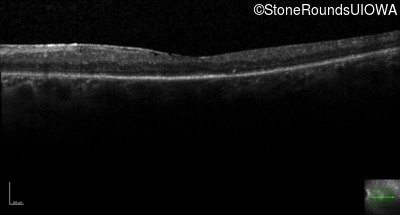

Age at visit: 59 years